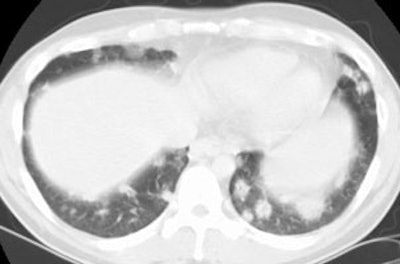

Open lung biopsy confirmed the diagnosis of BOOP. Following institution of therapy with steroids the lung lesions resolved. Click images to enlarge.